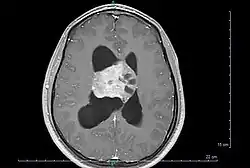

Axial T1-weighted gadolinium-enhanced MRI image showing an enhancing mass with cystic changes consistent with central neurocytoma in the right lateral ventricle.